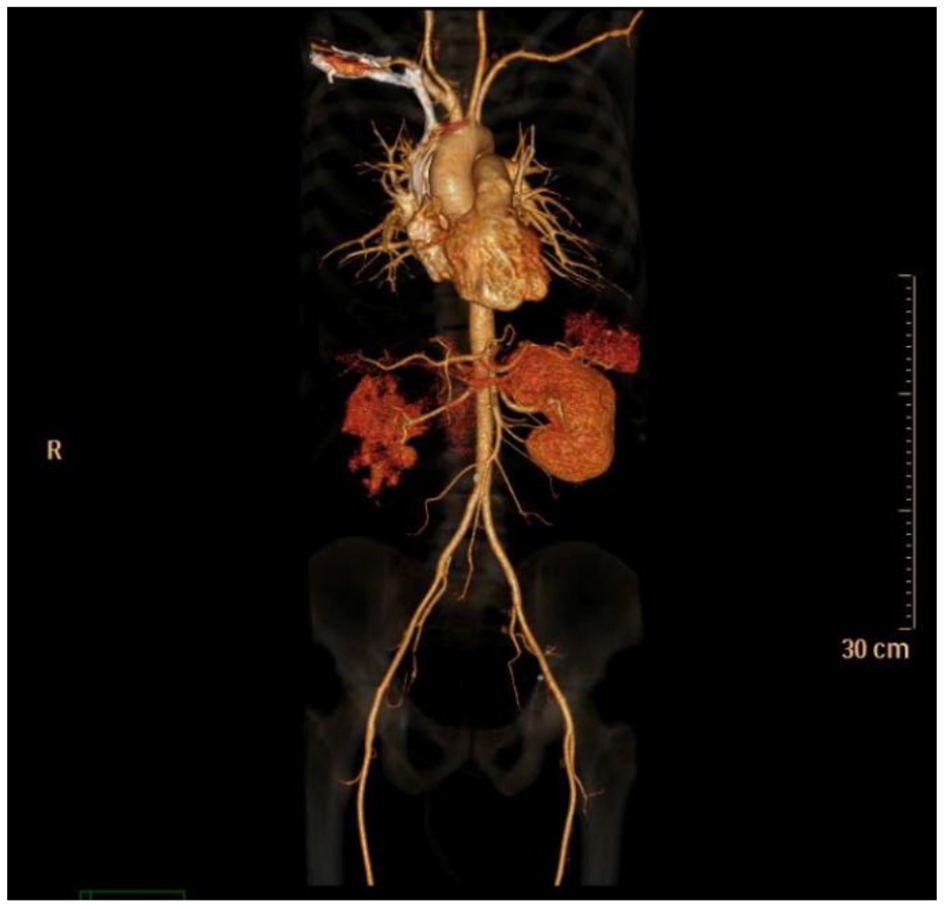

Lab tests were negative for antinuclear antibody, antinuclear cytoplasmic antibody, hepatitis B, hepatitis C and HIV. CT angiogram showed normal aorta, normal main renal arteries without evidence of dissection, luminal irregularity, or ostial stenosis (Figs. 3 and 4). Hypercoagulable study was negative for Lupus anticoagulant panel, antithrombin III deficiency, protein C and protein S deficiency and factor V Leiden mutation. After extensive workup, no apparent cause of renal infarct was found. Due to absence of underlying cause of atrial fibrillation or hypercoagulable disorder, no anticoagulation was started and he was discharged home on aspirin.

![]() Click for large image | Figure 3. CT angiogram anterior view. |